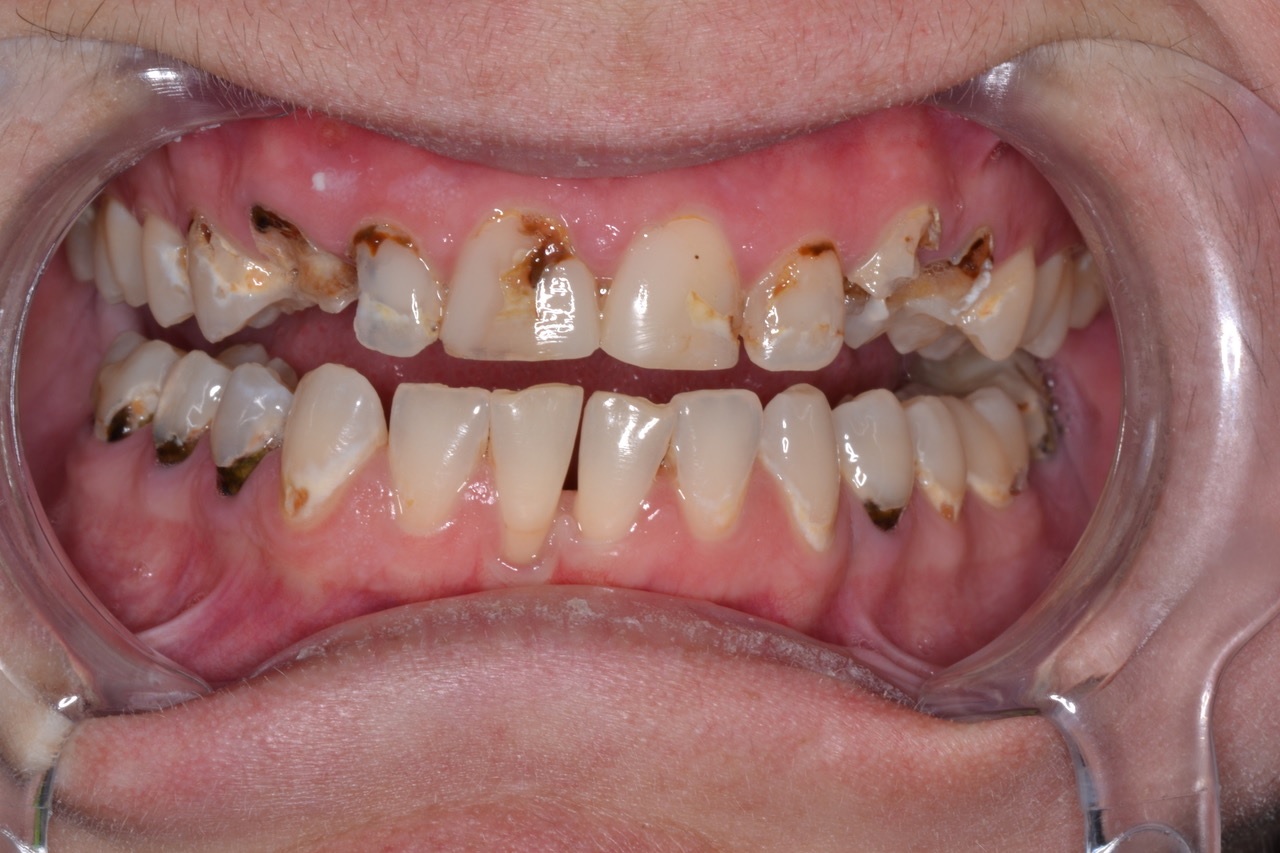

Using 3.5x loupes, caries detecting solution, and slow speed excavation, I removed massive

amounts of decay throughout the arch. (Fig. 3) There were pulpal exposures in teeth # 6, 10 and 11, and I immediately performed same-day root canals.

Figure 3

Figure 3. Shows teeth after caries

removal